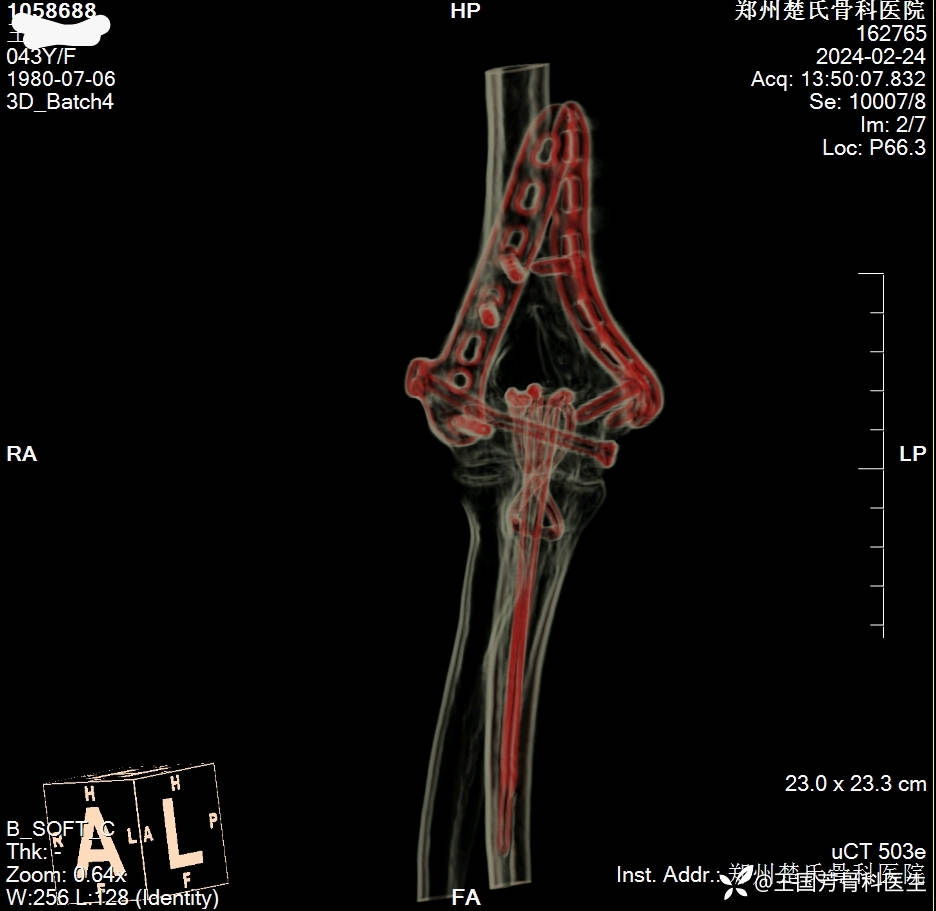

女,43岁,摔倒致右肘肿痛伴活动受限2小时入院。

诊断:肱骨髁间粉碎性骨折

伸直型损伤

Radjn分型:IV型

术后DR、CT

4.肱骨髁关节面一定解剖复位,双板坚强固定。